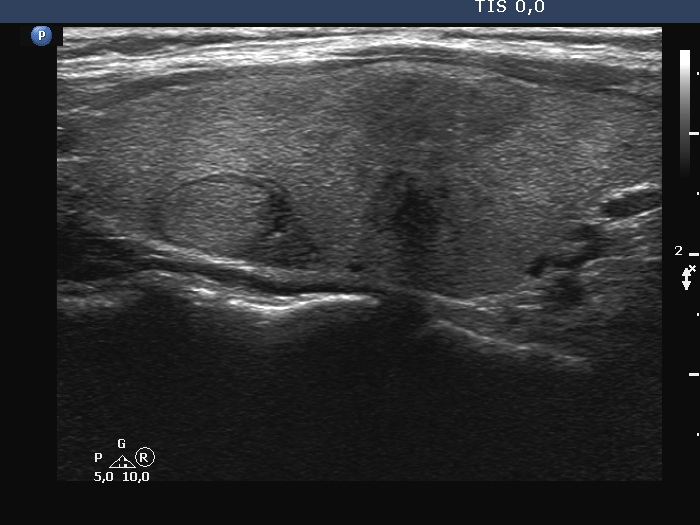

Ultrasonography. The thyroid was echonormal. There were three discrete lesions in the right lobe while several others in the left lobe. There was only one remarkable among them. This was in the ventral part of the right lobe. It was minimally hypoechoic, presented with partly irregular, partly blurred borders. Intranodular vascularity was detected.

The ultrasound and clinical presentation were remarkable, subacute thyroiditis had to be considered. I only mention that the neck discomfort ceased only after the removal of the tumor.